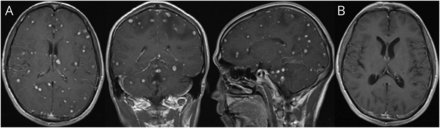

教学神经影像:大脑中的星空

一名30岁hiv阳性男性,有经常河浴史,出现头痛和发烧。神经系统检查显示脑膜刺激。脑MRI增强T1WI显示颅内弥漫性结节,信号强度高,呈星空状(图一个).血清IgG抗体裂体吸虫属采用ELISA法检测种。高通量测序证实脑脊液中存在血吸虫病。这些发现和缺乏肉芽肿疾病表明诊断为播散性脑血吸虫病。给予糖皮质激素和吡喹酮治疗(60 mg/kg, 2次/天,连续5天)。一年后,MRI随访显示病灶明显吸收(图B).